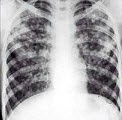

13、单项选择题 下述关于小肠Crohn病的影像表现,错误的是()

男,35岁,发热、贫血、血尿,有副鼻窦炎,结合X线图像,最可能的诊断是()

A.肺脓肿

B.周围型肺癌

C.肺转移瘤

D.肺结核

E.韦格肉芽肿